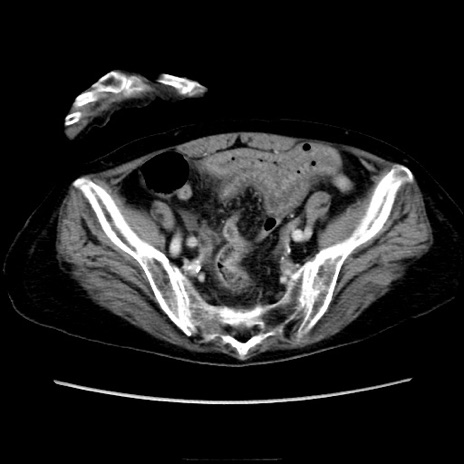

冠状断像

矢状断像